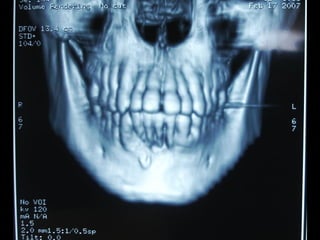

Eliminación de focos sépticos en bloque en paciente con osteitis

mandibular crónica

Osteitis

Imagen microscópica de osteitis, inicialmente existe una etapa de

osteoclastosis seguida por regeneración. No siempre el hueso

regenera en su totalidad y sigue el curso de cualquier inflamación

dejando un area de tejido fibroso que con el tiempo puede

calcificarse (hueso denso)

Manejo con antibióticos obligado

Revisión periódica